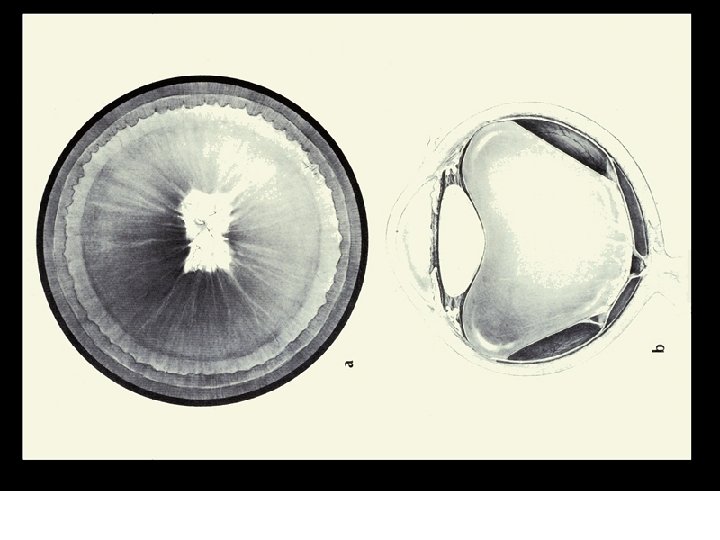

VII. PATHOLOGY AND AGE RELATED CHANGES z. A. Aging Changes y 1. Syneresis xa. a breakdown of the vitreous gel xb. fluid filled cavities form xc. 65 % of those over the age of 60 have syneresis xd. higher incidence in myopes

VII. PATHOLOGY AND AGE RELATED CHANGES xe. results in the fluid filled cavities enlarging and a possibility of the vitreous detaching from the retina xf. with detachment the patient reports "flashing lights" and "floaters" xg. more prone to retinal detachment

VII. PATHOLOGY AND AGE RELATED CHANGES y 2. Asteroid Hyalosis xa. hundreds of small spheres of calcium soaps are seen in the vitreous xb. are attached to the fibers of the vitreous so they move when the eye moves but always return to the same position xc. not associated with any systemic condition

VII. PATHOLOGY AND AGE RELATED CHANGES xd. more common in the elderly xe. no clinical significance xf. does not effect vision xg. 3 times more likely to be unilateral than bilateral